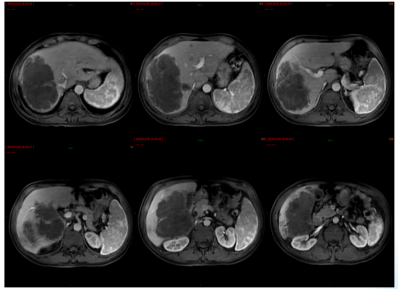

影像学检查:2024年7月30日,院外腹部CT显示乙状结肠管壁增厚,考虑肿瘤性病变(cT3N2,图1),2024年8月5日,肝脏MRI显示肝脏多发转移灶(侵犯门静脉右支、肝右静脉,图2)。2024年8月2日胸部CT显示双肺结节待排(图3)。

图1. 腹部CT

图2. 肝脏MRI